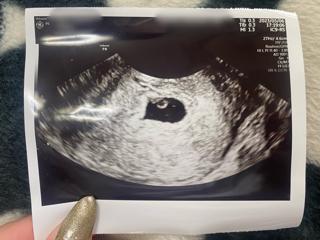

写真:5w6d:うりゆんさん

理想的なダイヤモンドリングが見えて感動しました。5w6dで既に心拍も確認できホッとしました。大きさはGS22mm, CRL2.7mmでした。

4人目ちゃんになります。